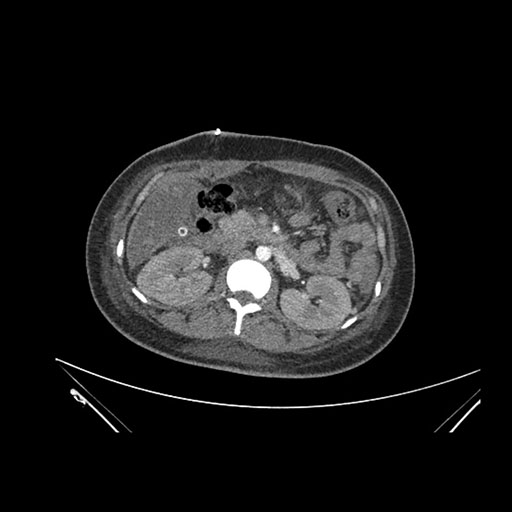

Imaging Analysis

Look through the patient's CT scan to identify any areas of concern for the necessary procedure.

Axial Arterial

Axial Venous